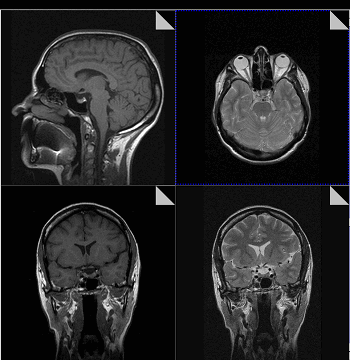

Сосудистые структуры средостения хорошо визуализируются на МР-томограммах ввиду того, что сигнал от просвета сосудов практически отсутствует. Вилочковая железа внутри периваскулярного пространства легче выявляется на МР-томограммах, чем при КТ. Форма, размер, интенсивность сигнала зависит от возраста. У детей вилочковая железа имеет промежуточную интенсивность сигнала, равную интенсивности сигнала от мышц или лимфоузлов. У взрослых интенсивность сигнала от вилочковой железы выше вследствие жировой инволюции, хотя она у разных людей варьирует. Размеры железы у пациентов старше 30 лет, выявленные при МРТ, лучше коррелируют с операционными находками, чем выявленные при КТ. Это связано с лучшей визуализацией инволютивных изменений при МРТ. Хотя вилочковая железа обычно располагается кпереди от крупных сосудов, она может располагаться и ретровазально. Определение локализации вилочковой железы важно для выявления связи аберрантной железы с переднемедиастинальной тимусной тканью но идентификации интенсивности сигнала.

Естественной контрастности МР-томограмм как правило достаточно для получения необходимой диагностической информации. В отдельных случаях для повышения чувствительности и специфичности метода необходимо дополнительное контрастирование. Исследование внутренних органов, в том числе средостения, основываются на быстрой диффузии парамагнетиков из сосудистого русла в опухолевом очаге. В некротических очагах, где нет кровотока, усиление не наблюдается.

Получение хорошего изображения на МРТ вилочковой железы затрудняется дыхательными движениями. Современный подход к визуализации вилочковой железы предполагает исследование на задержанном дыхании. Контрастирование лучше позволяет дифференцировать солидную и кистозную опухоли. Это связано с тем, что кистозный компонент может содержать примеси белка и крови, искажающие сигнал как на Т1-зависимых, так и на Т2-зависимых изображениях. Полное отсутствие контрастирования доказывает мягкотканную природу образования.